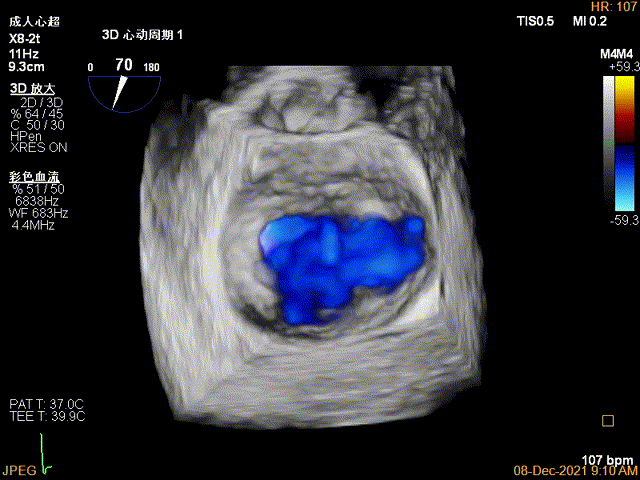

3D-VIEW验证结果

3D-Color-view验证残余分流位于外侧